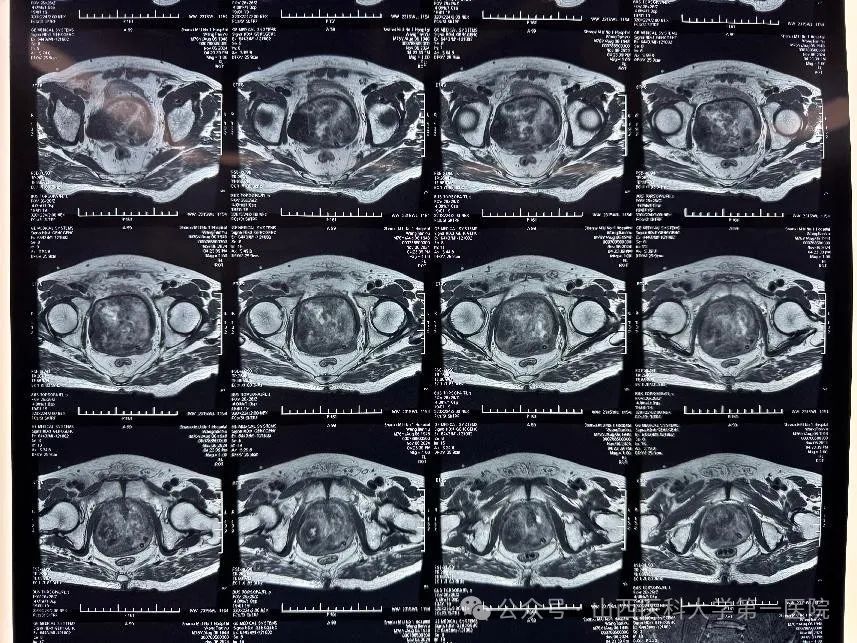

患者为76岁老年男性,进行性排尿困难5年余,半月前出现严重血尿,就诊于外院,给予抗休克、输血等对症治疗后,经尿道内腔镜下探查,考虑前列腺挤压出血,建议上级医院进一步诊治,遂来山医大一院就诊。患者入院后完善前列腺核磁,提示前列腺体积约8.1cm*7.9cm*9.2cm,约306cm³,属于极重度前列腺增生,是普通人前列腺的十几倍。经过全科室讨论后,考虑患者既往高血压、糖尿病、心脏病、脑梗等病史,前列腺体积巨大,经尿道手术空间狭小,操作难度大,手术时间长,决定行机器人腹腔镜前列腺切除术,术中视野更大,操作更精细,出血更少,同时经膀胱入路能最大程度保护患者尿控,使患者更受益。